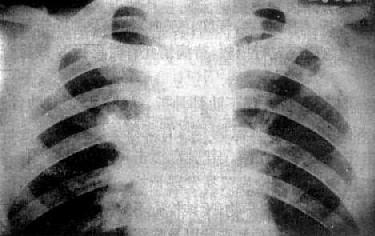

(2)亚急性或慢性血行播散型肺结核:系少量结核杆菌在较长时间内多次进入血流播散至肺部所致。患者抵抗力较强,症灶多以增殖为主,临床症状可不明显或有反复的发热、畏寒或轻度结核中毒症状如低热、盗汗、无力、消瘦等。

由于病灶系多次血行播散所形成,故X线表现为大小不一、密度不同、分布不均的多种性质的症灶(图3-1-23)。小者如粟粒,大者可为较大的结节状,主要分布于两肺上、中野,下野较少。早期播散的症灶可能已经钙化,而近期播散的病灶仍为增殖性或渗出性。本型结核发展较慢,经治疗新鲜病灶可以吸收,陈旧病灶多以纤维钙化而愈合。恶化时病灶可融合并形成空洞或逐渐转为慢性纤维空洞型肺结核。

图3-1-23 慢性血行播散型肺结核

两肺野布满大小不一、密度不同、分布不均的病灶,

下野较少,膈位置低而平